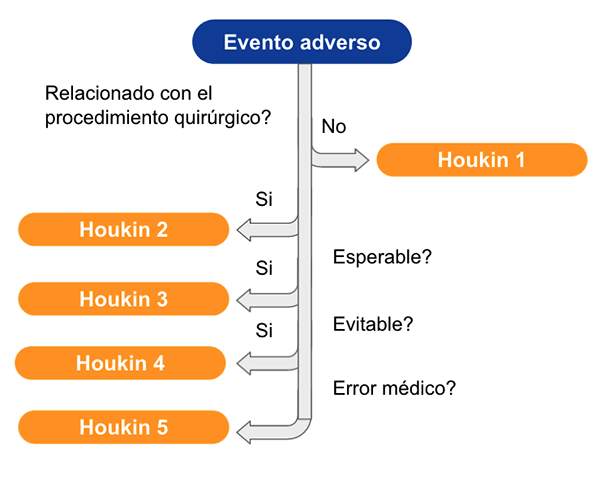

Utilizamos ambas escalas ya que aportan distinta información, la cual se complementa para evaluar la aparición de un evento adverso. La propuesta por Landriel et al. 11 se basa en la descripta por Dindo y Clavien 5, desarrollada para pacientes adultos en cirugía general. En ella, se incluyen todos los pacientes que presentan un desvío del post operatorio esperable, que hayan requerido o no algún tipo de intervención, ya sea farmacológica, invasiva, etc. En esta se valora como la complicación afecta al paciente, generando morbilidad y se clasifica por grado de severidad, desde la colocación de terapia farmacológica hasta el óbito. Tipo 1a: Desviación del post operatorio esperable, que no requiere tratamiento farmacológico. Tipo 1b: Desviación del post operatorio esperable, que requiere tratamiento farmacológico. Tipo 2a: EA que requiere intervención sin anestesia general, ya sea cirugía, endoscopía o intervencionismo. Tipo 2b: EA que requiere intervención con anestesia general, ya sea cirugía, endoscopía o intervencionismo. Tipo 3a: EA que compromete la vida del paciente, y requiere el ingreso a unidad de cuidados intensivos y compromete 1 solo sistema u órgano. Tipo 3b: EA que compromete la vida del paciente, y requiere el ingreso a unidad de cuidados intensivos y compromete más de 1 sistema u órgano. Tipo 4: Óbito del paciente. Mientras que en la clasificación propuesta por Houkin et al. 10 se determina la probabilidad de que el evento adverso sea asociado al procedimiento quirúrgico, y el grado de relación entre ellos (Figura 1). Tipo 1: EA no relacionado al procedimiento quirúrgico, por ejemplo la aparición de infección urinaria luego de una cirugía de colocación de sistema de derivación ventrículo-peritoneal. Tipo 2: EA relacionado al procedimiento quirúrgico, no esperable de acuerdo a la patología y el tratamiento elegido. Por ejemplo, la aparición de un déficit del 6to nervio craneano luego de la cirugía de un tumor hemisférico supratentorial. Tipo 3: EA relacionado al procedimiento quirúrgico, esperable de acuerdo a la patología y el tratamiento elegido, por ejemplo, un déficit braquiocrural contralateral asociado a la exéresis de un tumor en área motora primaria. Tipo 4: EA relacionado al procedimiento quirúrgico evitable, por ejemplo, la lesión del 3er nervio craneano en la cirugía clipado de aneurisma comunicante posterior, habiendo visto y cortado dicho nervio durante el procedimiento. Tipo 5: EA relacionado al procedimiento quirúrgico, por un error médico, ya sea por tratamiento insuficiente, falla en la técnica quirúrgica, indicación inadecuada o enfoque diagnóstico y tratamiento erróneo. Por ejemplo, la colación del sistema distal de una derivación ventrículo-peritoneal en el espacio pre-peritoneal.

Figura 1: Algoritmo para utilización escala de Houkin